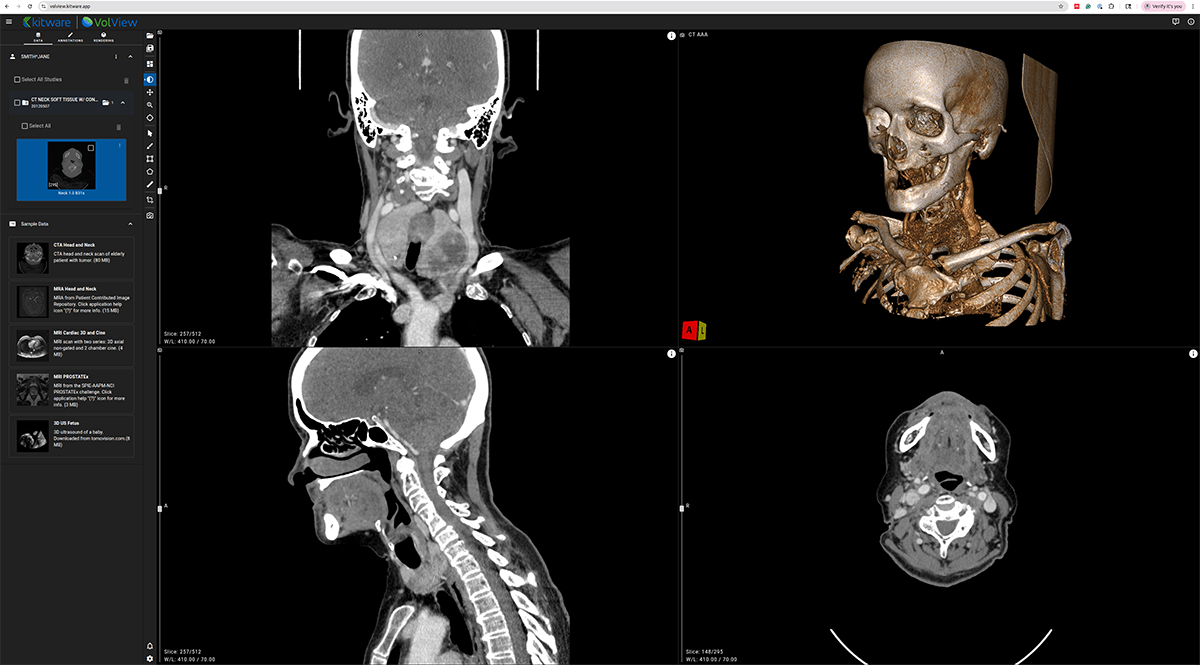

VolView is Kitware’s zero-install, browser-native medical imaging platform that brings workstation-class visualization directly into a web browser. Unlike traditional imaging applications that require complex installation procedures, specialized hardware, or remote rendering servers, VolView runs entirely on the client. This means all interaction scrolling through slices, adjusting window/level, cinematic volume rendering, multiplanar reconstruction happens locally on the user’s device with immediate responsiveness.

At the core of VolView is a modern web technology stack built for high-performance scientific visualization. WebGL and WebGPU provide GPU-accelerated rendering directly in the browser, while VTK.js powers interactive 2D and 3D visualization capabilities rooted in decades of Kitware’s experience developing VTK, ParaView, and other large-scale visualization systems. For image processing, ITK-WASM delivers fast, in-browser operations for reading, decoding, resampling, measuring, and manipulating medical volumes using WebAssembly. Together, these components allow VolView to support a wide array of formats including DICOM, NIfTI, NRRD, and MHA without plugins or backend servers.

NV-Segment-CTMR — 3D Foundation Segmentation

NV-Segment provides high-quality automatic and interactive segmentation for a wide range of anatomical structures. Within VolView, it enables users to quickly generate volumetric labels, refine results through interactive adjustments, and incorporate segmentation into downstream visualization or analysis workflows.